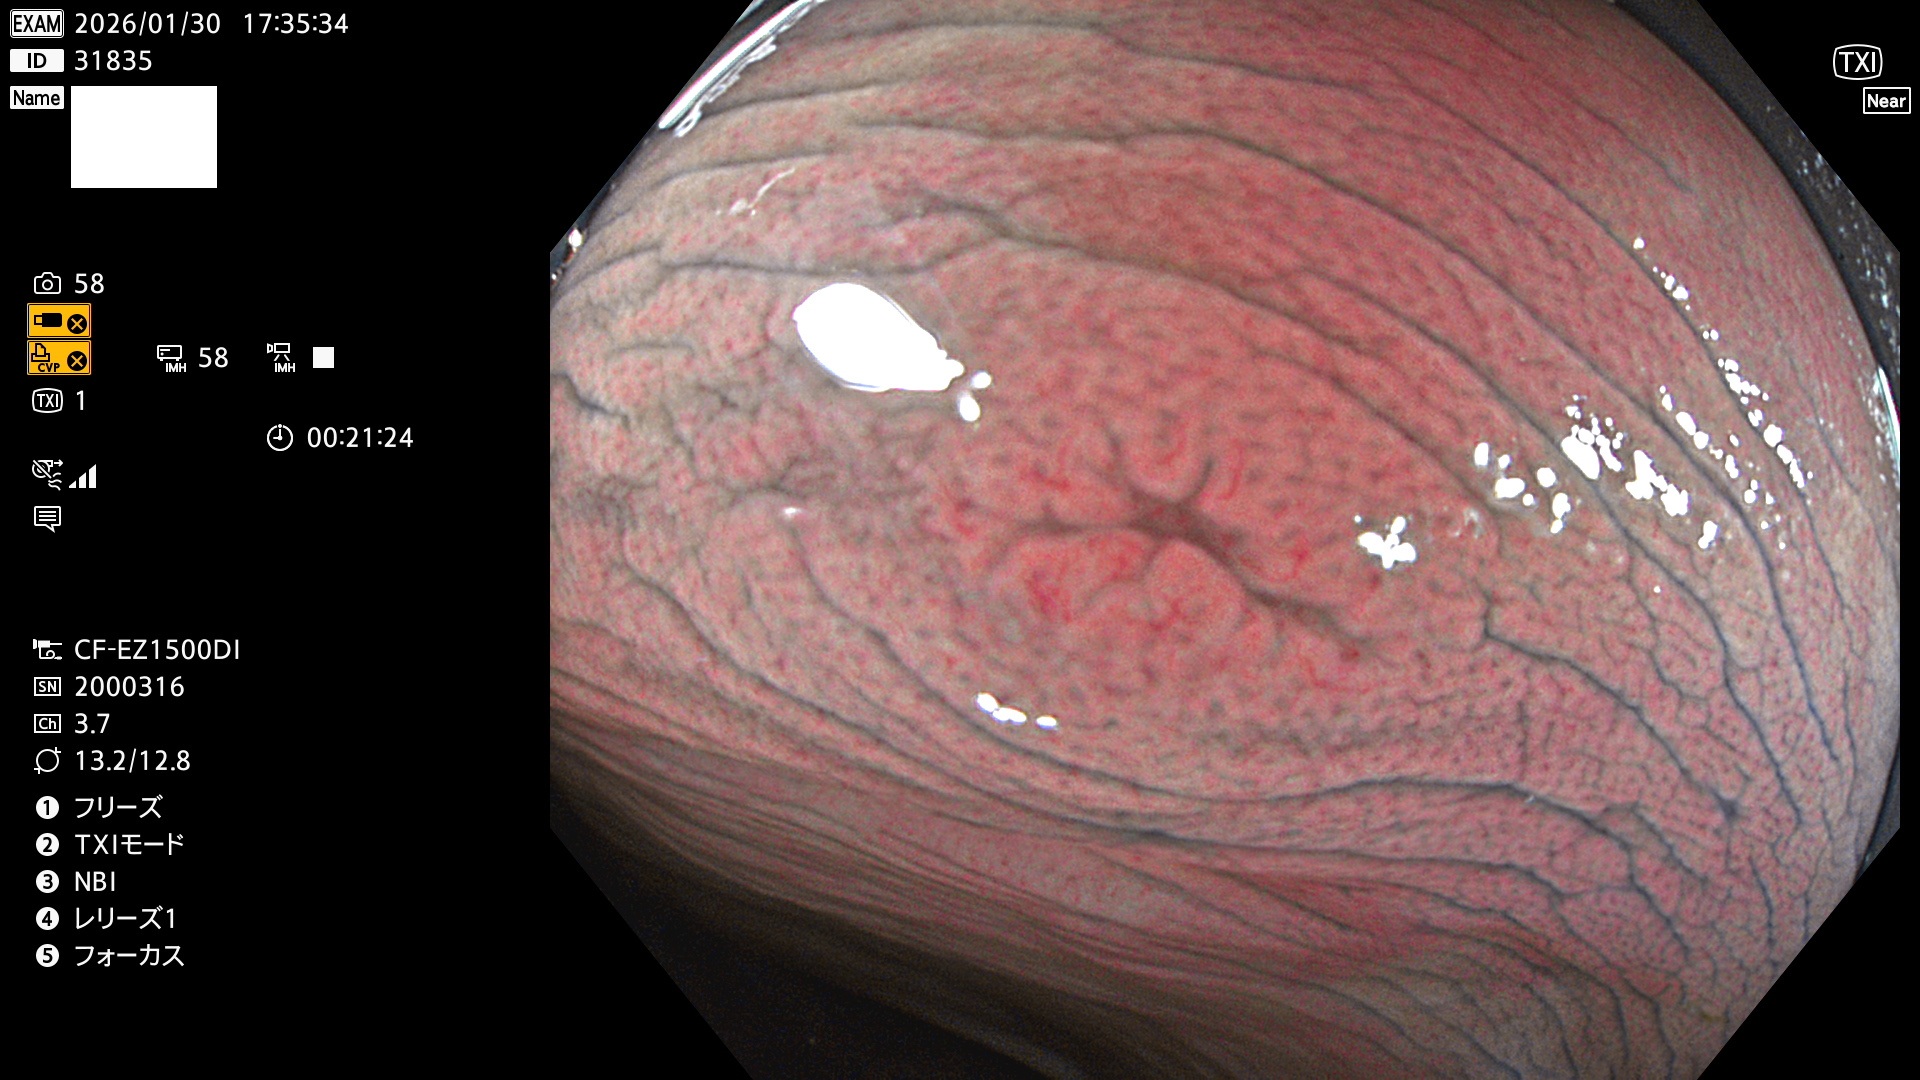

完全に平坦な物をUb、陥凹している物をUcと呼びます。Ubは認識が困難で、Ucはびらん(炎症)と紛らわしいために見落とされやすく、「内視鏡後・大腸癌」の原因になります。

専門的)Uc=De Novo癌? 内視鏡の解像度が低かった時代、このような説もありました。しかし今日の高精度内視鏡では良性の微小なUc型腺腫(APC遺伝子異常の腺腫)が日常的に見つかります。Ucこそが多段階発癌(Adenoma-Carcinoma Sequence)のMain Routeです。

毎週の検査(木・金・土・日)に発見されたUbとUc型・腺腫を、その週の日曜の夜にUPし1週間、提示します。

2026年1月29日〜2月1日の4日間(40件)10個 (Uc_ADR=10個/40人=25%)